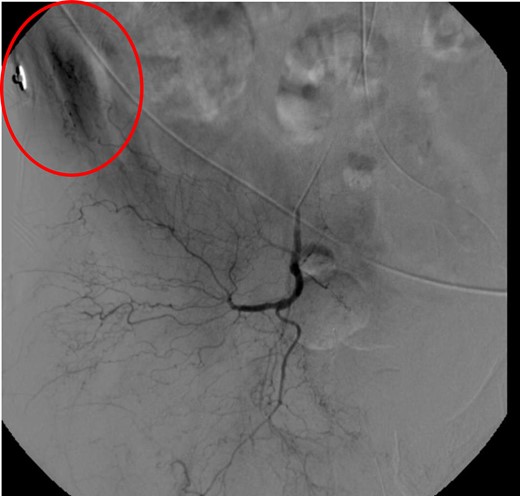

CT abdomen/pelvis with contrast was performed and a blush of contrast was noted posterior to the right pubic bone. Prior to taking patient for exploratory surgery, he was transferred to the interventional radiology suite where a pelvic angiogram was performed revealing an abnormal blush localized to the distal branches of the right iliolumbar artery (Fig. 2). Delayed phase of the angiogram demonstrated early venous filling consistent with a traumatic arteriovenous fistula which was embolized with 300–500 µ of embospheres and three 3 × 2 microcoils (Figs 3 and 4).

CT angiogram demonstrating microcoil embolization of AV fistula.